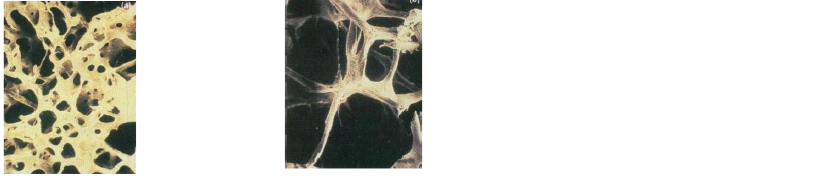

Pengeroposan tulang adalah istilah awam untuk suatu kondisi kerapuhan tulang akibat berkurangnya kepadatan/densitas massa tulang. Pengeroposan tulang ini cukup lazim terjadi pada usia senja, meskipun secara umum dibedakan menjadi dua macam yaitu: pengeroposan pasca menopause dan pengeroposan senilis (masa tua).  Kepadatan tulang manusia pada umumnya bertambah pada masa muda, mencapai puncak pada usia dekade 3 (25 – 30 tahun), dan menurun seiring bertambahnya usia hingga akhir masa hidup.   Dalam pengamatan menggunakan mikroskop struktur tulang tetap tampak normal hanya bentukan jaring-jaring tulang menjadi tipis dan mudah patah.

Gambar:  tulang normal                          Gambar:  tulang keropos